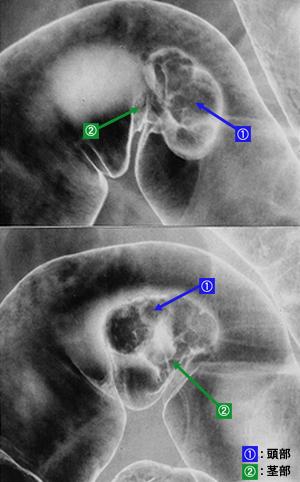

A case of sigmoid colon adenoma which was removed by an endoscopic polypectomy.

Benign epithelial tumor/Adenoma

Large intestine(Colon)/Sigmoid colon

X-ray

Type 0/I (Ip) Pedunculated type

25 - 29